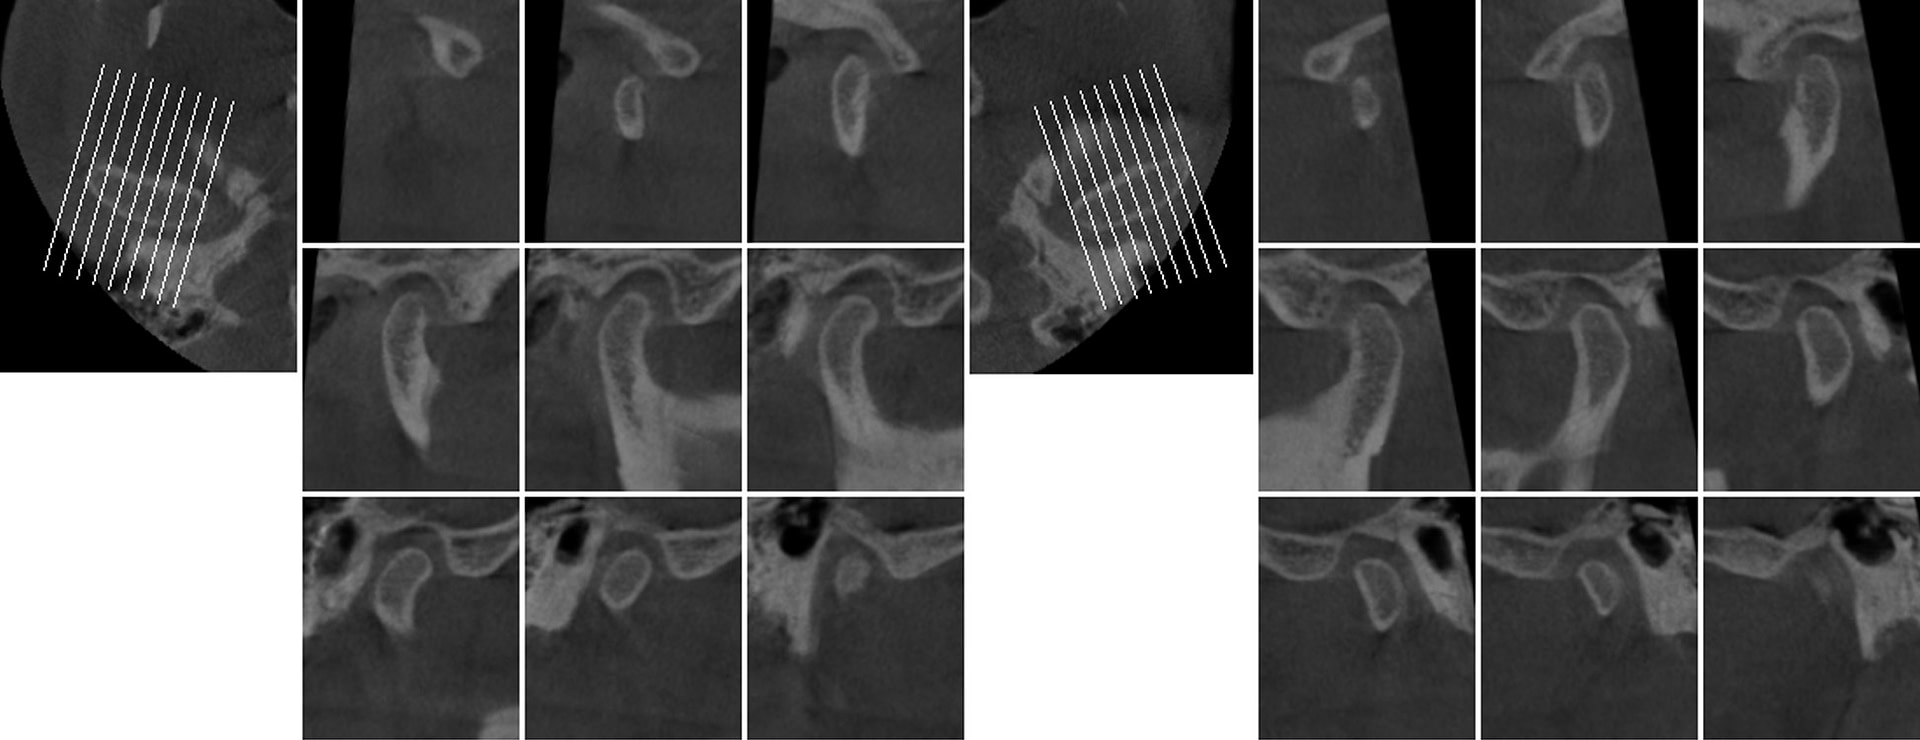

Third Molar Report

A single-third molar is selected to evaluate for extraction.

Generates slices in 3 directions and highlights the position of the inferior dental canal.